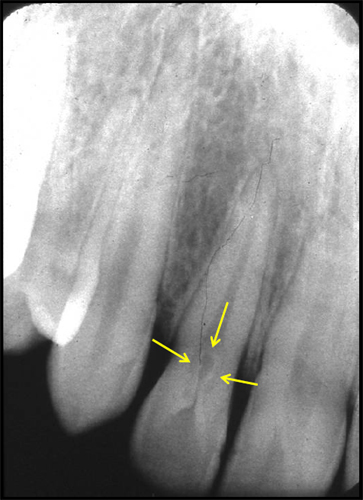

What’s happening with the tooth in the marked area?

Dens invaginatus